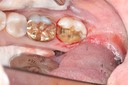

Mark Chun #29 amalgam removal